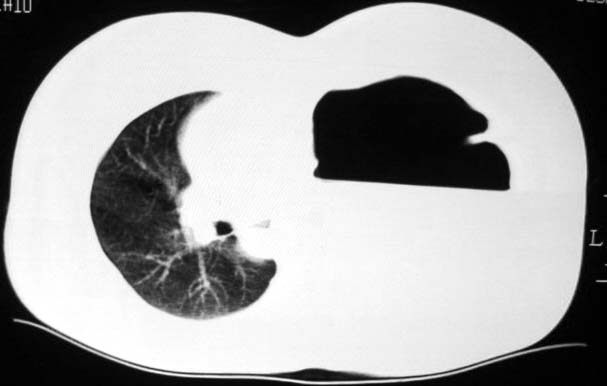

标题: CT5517:女性、24岁,反复胸痛、气促不能平卧半月。 [打印本页]

标题: CT5517:女性、24岁,反复胸痛、气促不能平卧半月。

左肺可见二个含气或液气的囊状影,左肺段支气管、左肺动脉显示不清,纵隔右移,考虑:左肺支气管肺囊肿,左肺发育不良,纵隔疝。

液气胸 怎么会有2 个大腔?

左肺发育不良、支气管囊肿 应该纵隔左移的多吧

还是个膈疝